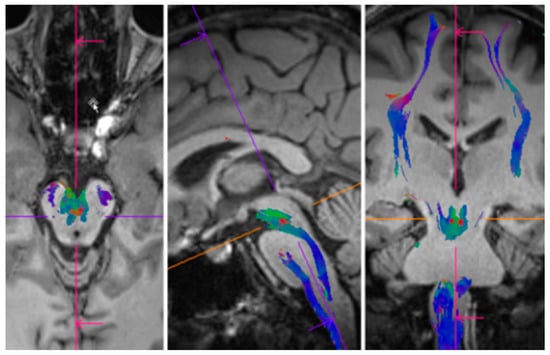

2.7. MR-Imaging

3.5. Analysis of MR-Imaging